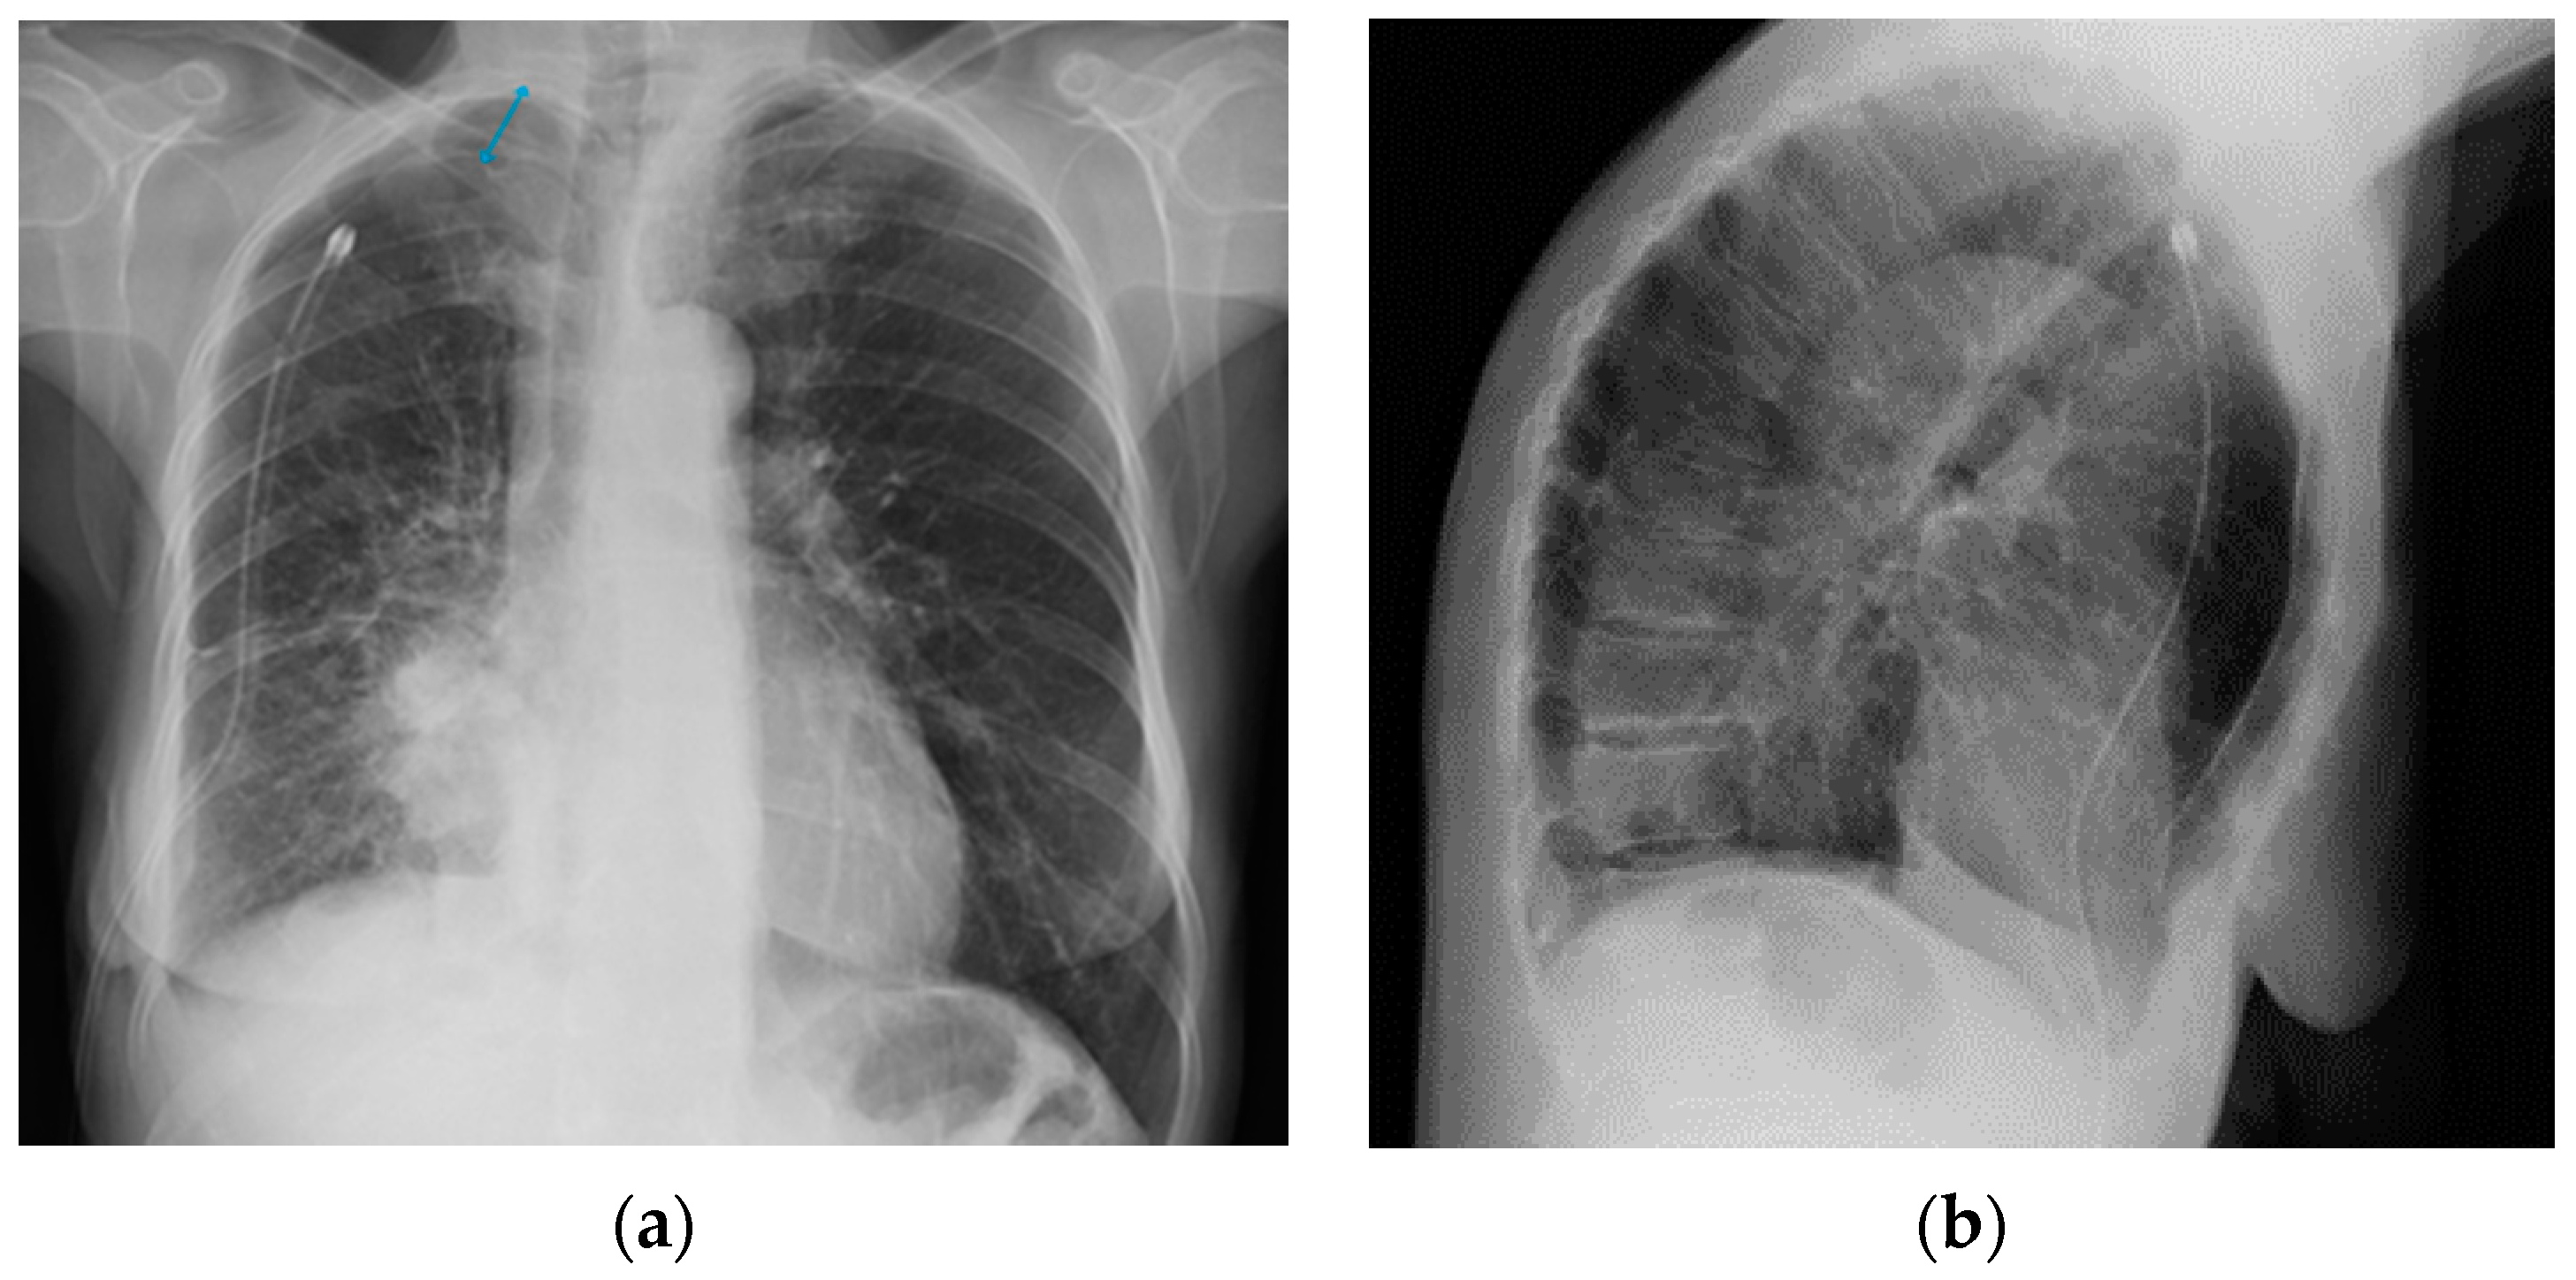

Figure 28.

Right apical chest drainage tube in patient with right pneumothorax (blue arrow) on PA (a) and LL (b) projections.

Figure 29.

Post-operative CXR illustrating two chest tubes with their tip in the right apical region. Note that whereas in the PA projection (a), the tubes seem to follow the same course, the LL view (b) clearly differentiates between an anterior and a posterior course.